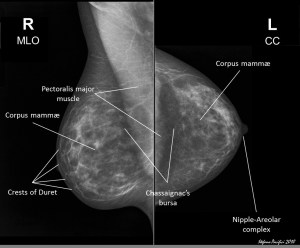

Image tirée du site Radiopaedia.